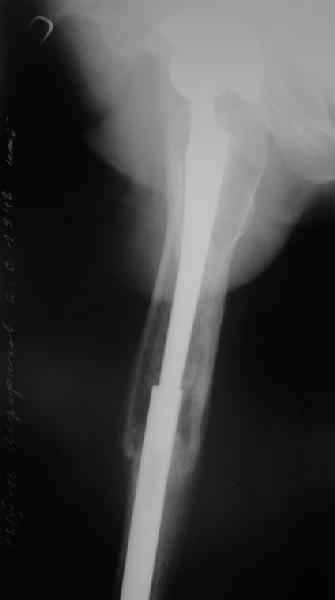

Пациенту 72 года, оперировался 11 лет назад в ГКБ15 Москва. Судя по снимку ножка споторно фирмы матис. Вряд ли сможем найти такую же для примерки.

Дополнительные снимки